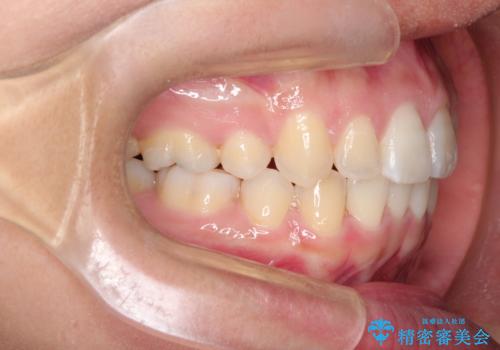

前歯が八重歯でガタガタ ワイヤーによる抜歯矯正

前歯の重度のガタガタで、八重歯もある状態でした。

上顎両側と左下の前から4番目の歯と、右下の乳歯を抜歯して矯正することとなりました。

乳歯を抜歯することにより、通常よりは治療期間を要してしまいましが、前歯のガタガタもなくなりきれいな歯並びになったと喜んでいただけました。